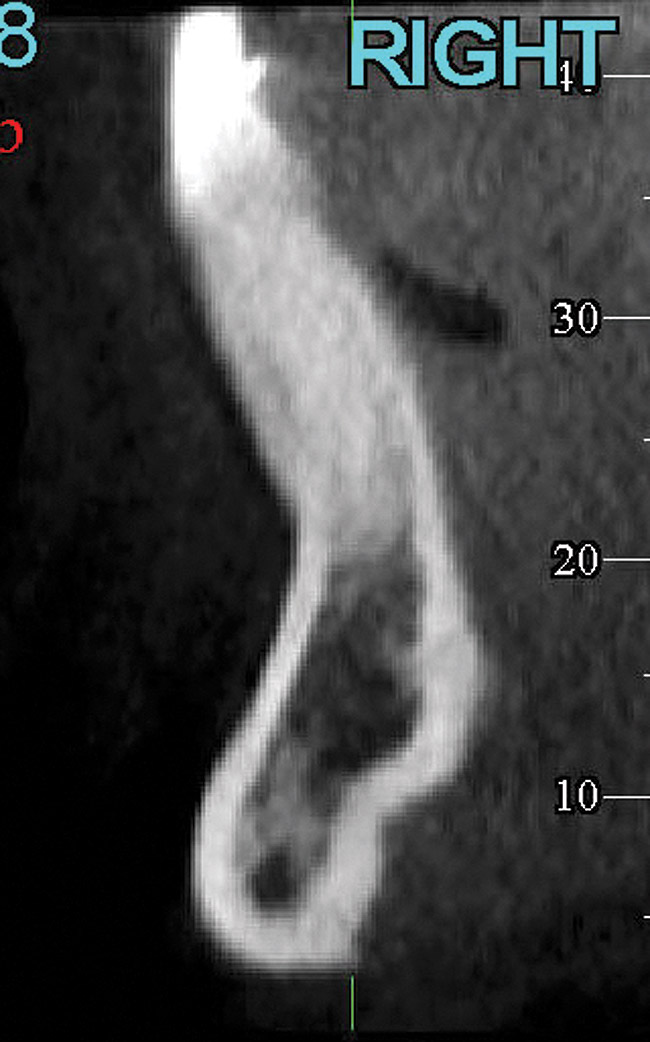

Fig 5. CBCT sagittal view of the same patient showing thin/no bone on the lingual aspect.

Figure 5

In cases with thin lingual bone, as measured on CBCT (<2.5 mm at a level of 8 mm apical to the CEJ), orthodontic treatment is not advisable, leaving surgical root coverage as the only option. However, the prognosis for this procedure is poorer, because the predominant cause is not addressed. Figure 4 shows the frontal clinical view of a patient with a hyperdivergent growth pattern who presented with post-orthodontic GR of a labially displaced lower central incisor. The sagittal CBCT view (Figure 5) shows complete absence of lingual bone, which contraindicated orthodontic tooth repositioning.